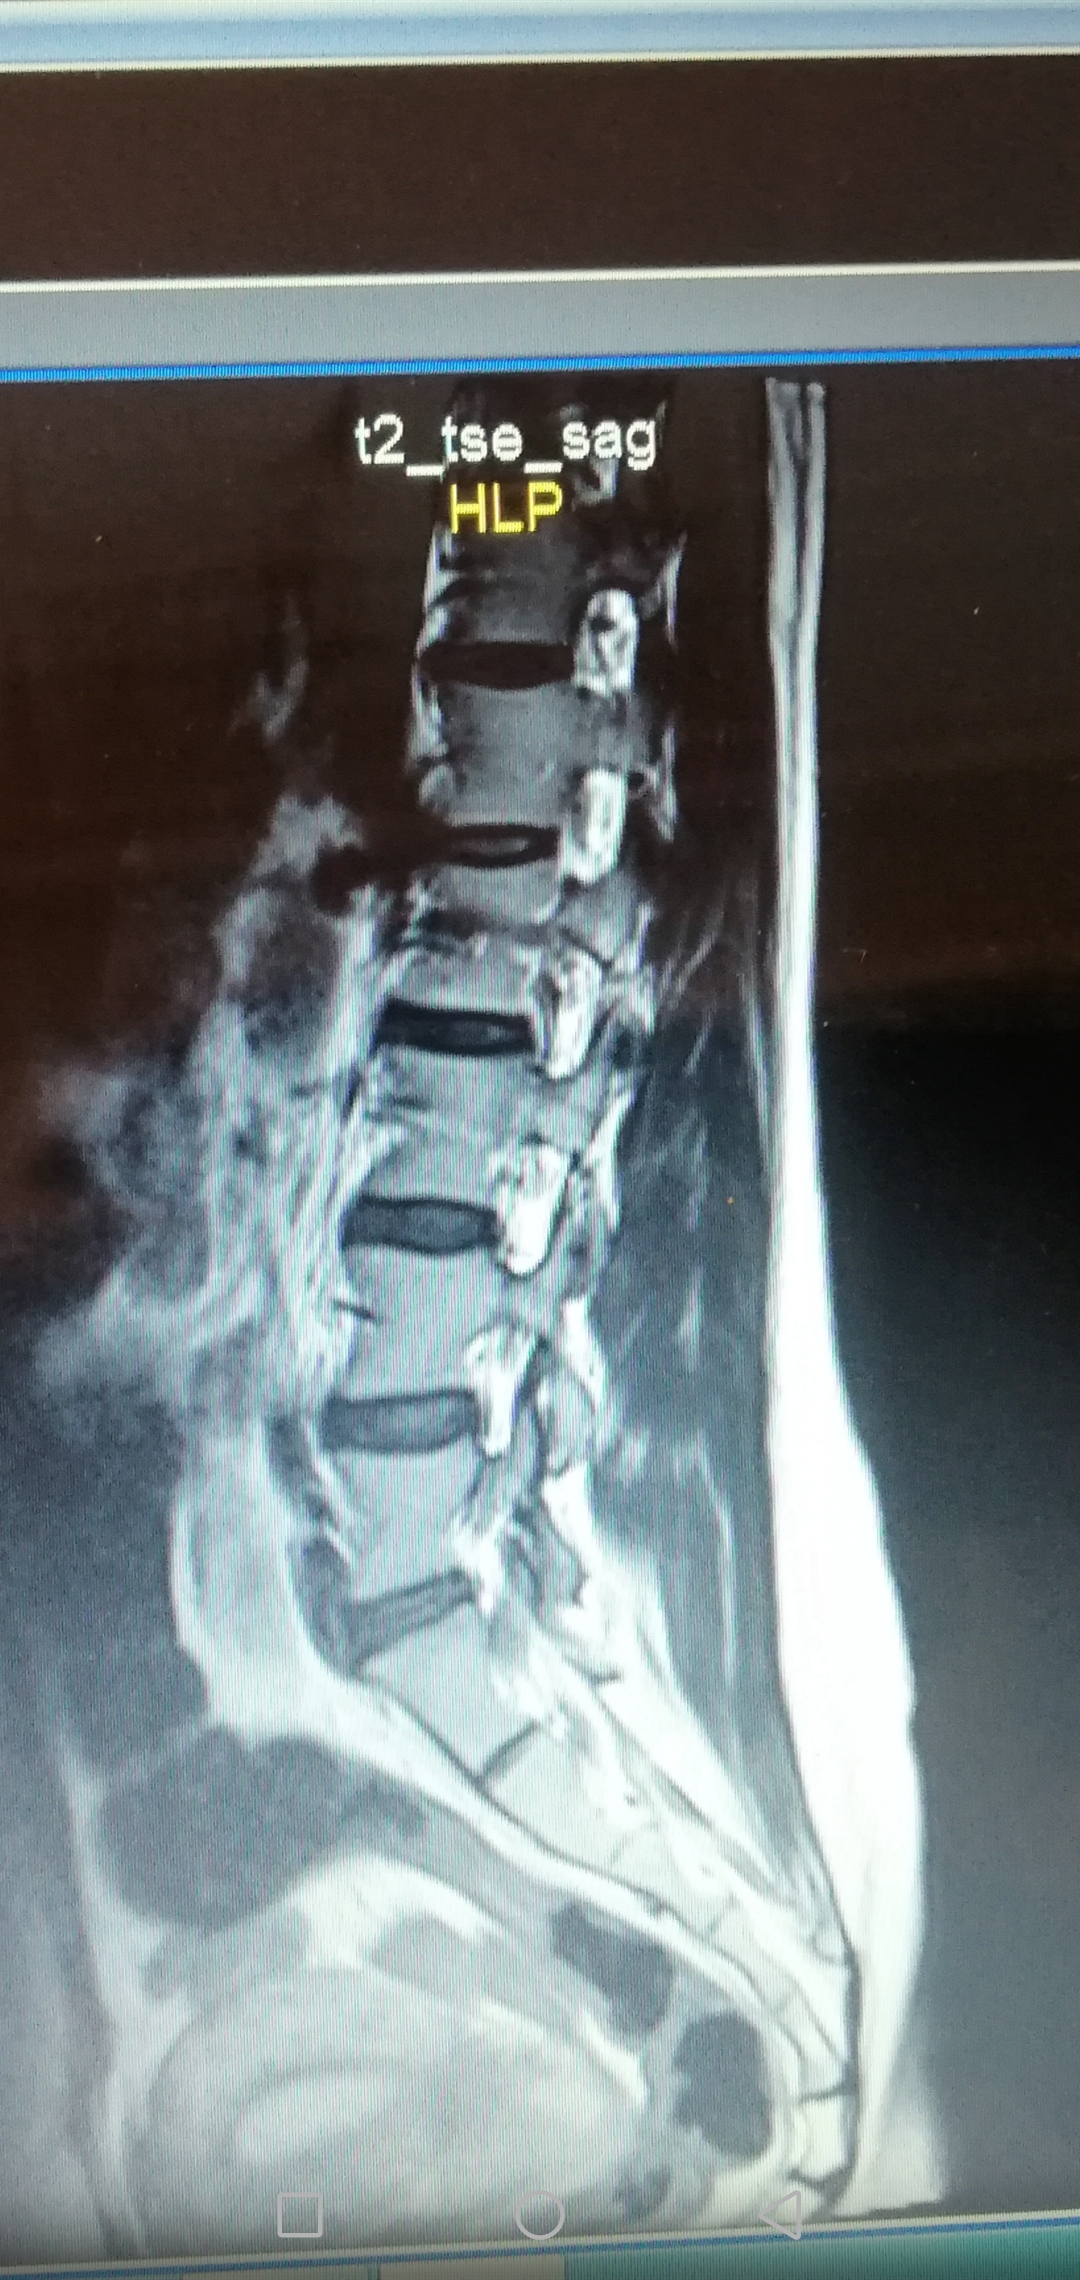

عشقم_اناره مدیر استارتر عضویت: 1398/06/13 تعداد پست: 5812 عنوان کسی هست تفسیره ام ار ای 😢 81 بازدید | 7 پست 🌹 1403/12/01 | 08:40 0 نفر لایک کرده اند ... گزارش تاپیک نامناسب

عشقم_اناره مدیر استارتر عضویت: 1398/06/13 تعداد پست: 5812 تفسیر ام آر آی کار دکتر متخصص هستش تا اون حد نمیخام